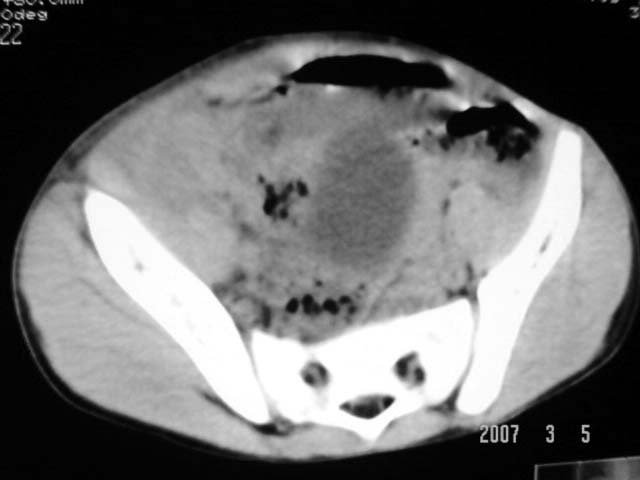

以下是引用dyqct在2007-3-5 10:28:00的发言:[br]右髂窝肿块。[br][br][br][br]